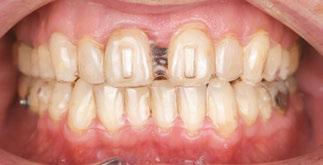

Drs. Claudia Pinter and Stanley Liu illustrate a protocol to improve nasal breathing in orthodontic care 31